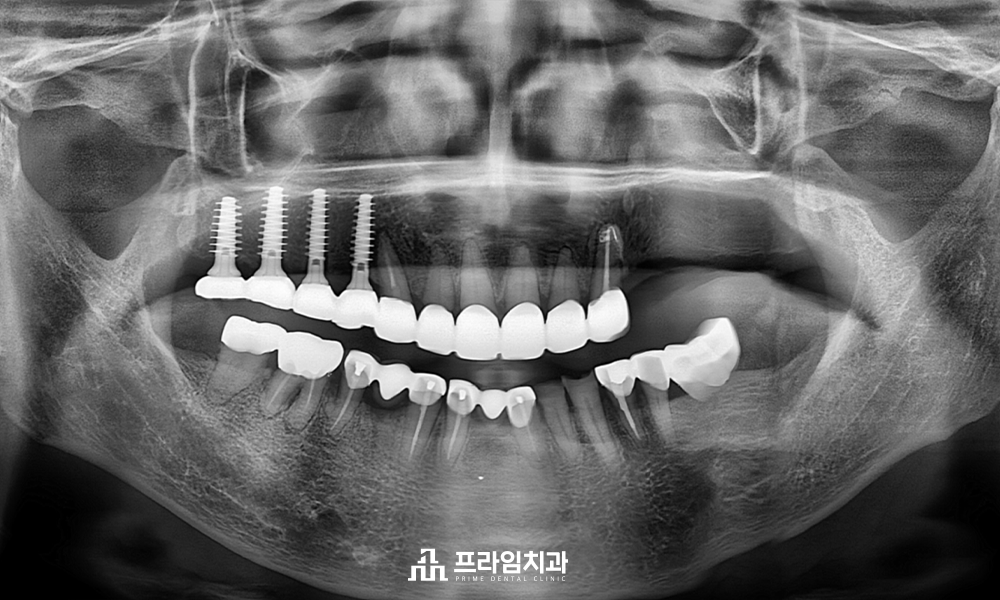

임플란트를 식립 할 때 위아래의

교합을 정교하게 맞추기 위해 아래쪽

보철물을 새로 제작하였으며,

.

닳아있던 앞니 보철치료까지 완료하여

2년 후 정기 검진을 오셨을 때

촬영한 파노라마 사진입니다.

매직 코어 임플란트의 식립을

통해 빠른 회복과 더불어 환자분의

꾸준한 관리로 건강하게 유지가

잘 되고 있음을 알 수 있었습니다.

어금니의 임플란트와

앞니 보철치료까지

완료되고 난 후에는 기존 거꾸로

물리고 있었던 교합까지

회복할 수 있었습니다.